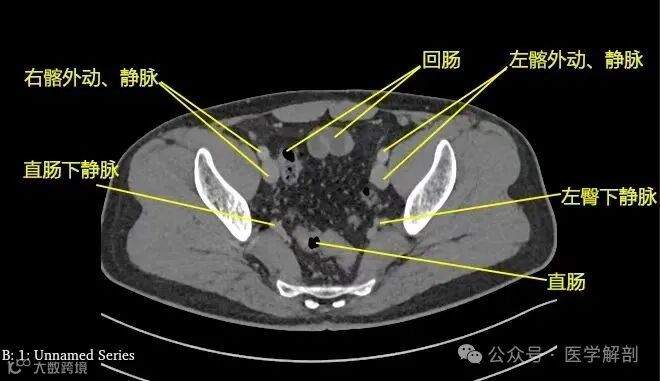

第四骶椎中部

第四骶椎平面标注